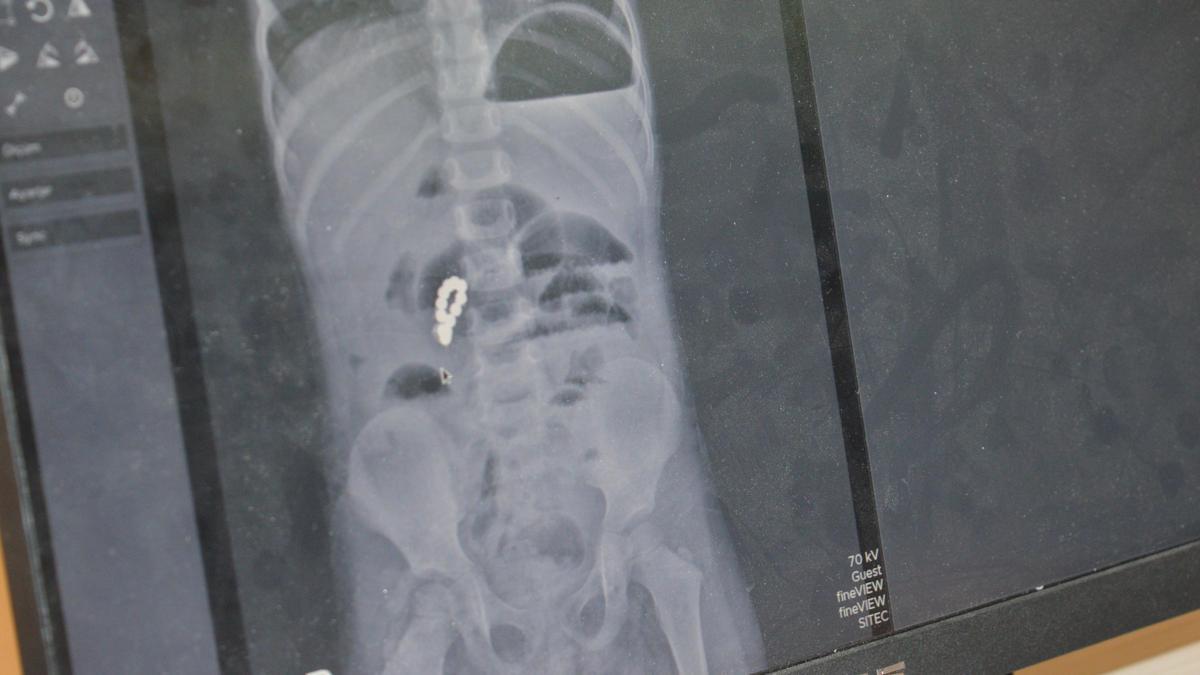

Arabesk müziğin tanınan ve sevilen sanatçılarından Hakan Taşıyan, geçirdiği kalp krizi nedeniyle hastaneye kaldırıldı.

Sağlık durumunun ciddiyetini koruduğu belirtilen Taşıyan için anjiyo uygulanıp uygulanmayacağına ilişkin doktorların değerlendirmesi sürüyor.

Bu dizide Kemal karakterini canlandırdı. 52 yaşındaki Taşıyan, hem karaciğer hem de böbrek nakli geçirmişti.